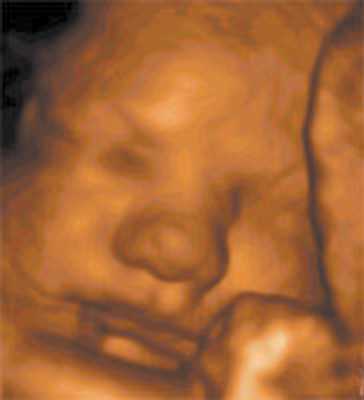

Цель 3D-ультразвукового исследования состоит в создании объемного изображения в отличие от двухмерного метода, создающего плоскостные сечения [6, 11]. Объемная картина получается при сканировании смежных сечений — это объем пространства пирамидальной формы (рис. 3, 4).

Рис. 4. Плод, 32 недели, 3D-ультразвуковое исследование / Fig. 4. Fetus, 32 weeks, 3D

На полученных сонограммах у 15 беременных визуализировались все 20 зубных зачатков. Лицо плода помещалось на экран таким образом, чтобы можно было вывести профиль, а сдвиг и вращение изображения давали возможность осмотра верхней и нижней челюсти (рис. 8, 9). У трех беременных визуализация была затруднена. С использованием плоскостей сканирования, оптимизированных для исследования конкретного органа, осуществлялась визуализация нижней челюсти целиком, включая сочленение с верхней челюстью.

Рис. 8. Лицо плода / Fig. 8. Fetal face